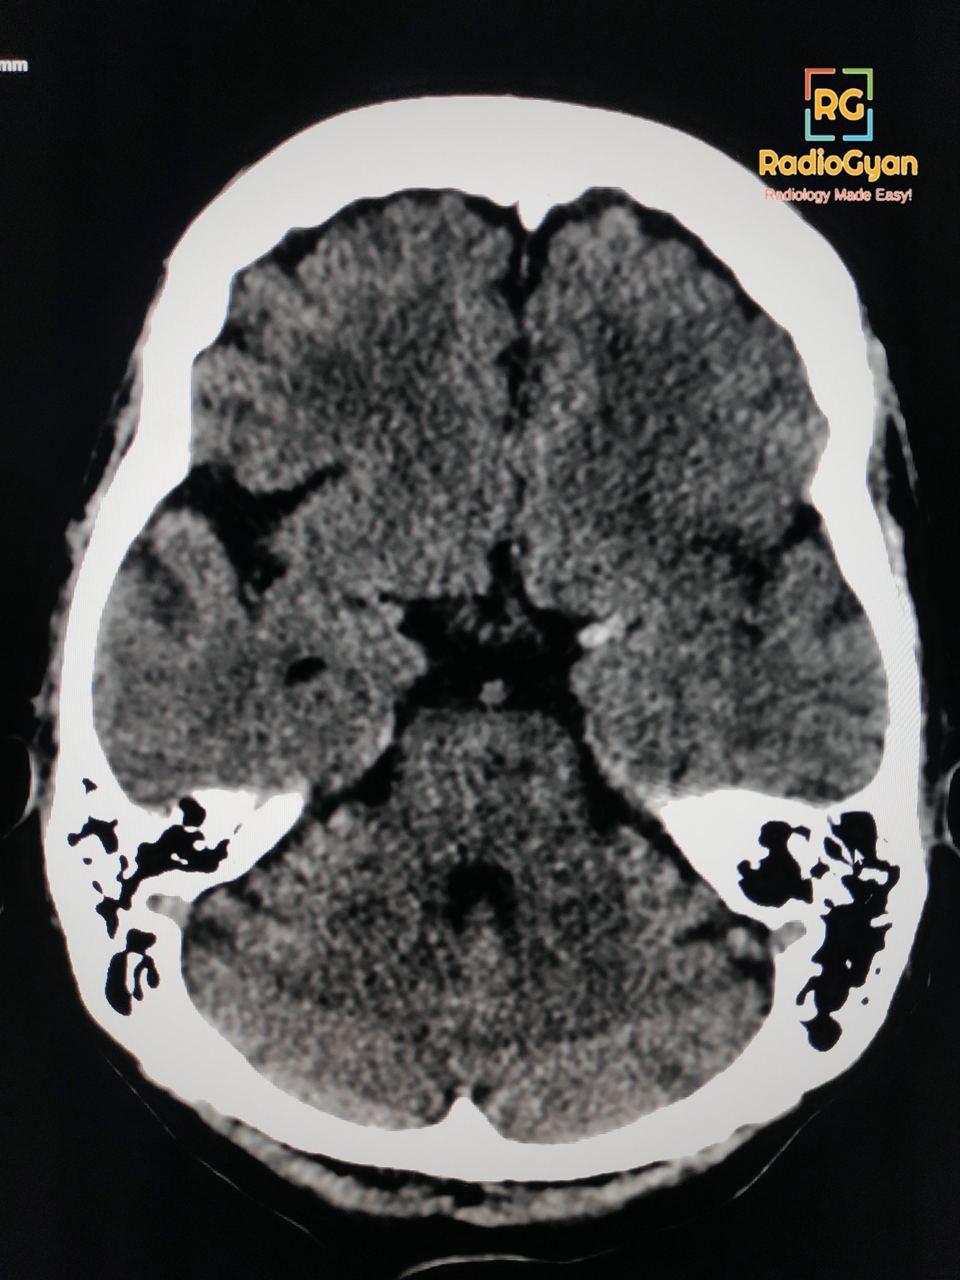

The dense MCA sign is caused by the presence of intraluminal thromboembolic material within the middle cerebral artery, which appears hyperdense on non-contrast CT scans. This condition is often seen early in acute ischemic stroke.

The dense MCA sign is named due to the focal hyperattenuation (increased density) observed in the middle cerebral artery, which is visually distinct from the surrounding brain parenchyma on CT imaging.

The sign is a result of the higher density of the blood clot compared to the surrounding brain tissue. This increased density is visible on CT scans because the fresh thrombus contains more hemoglobin and other blood components than the surrounding brain tissue, making it appear brighter or more dense. The dense MCA sign therefore indicates an occlusive thromboembolism causing arterial ischemia in the middle cerebral artery territory.